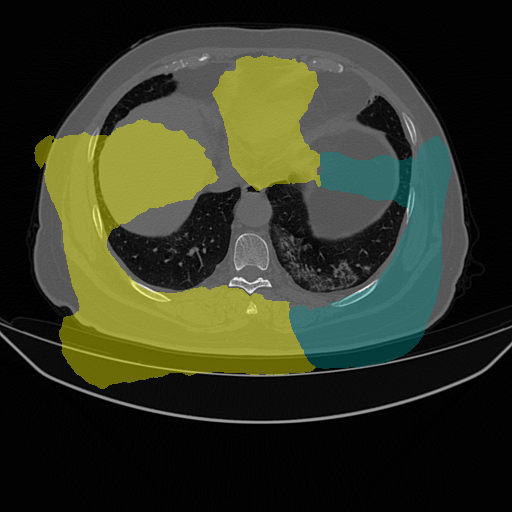

| Lung Segmentation (COV, 2019) Left lung (Cyan) Right lung (Yellow) | ![]() |

| (e) CT slice | (f) FGSM | (g) PGD | (h) Ours | |

While recent studies of adversarial attacks mainly focus on natural images, the research of adversarial attacks in the medical image domain is desired as there are significant differences between two domains. Beyond regular RGB cameras, there are various types of medical imaging equipments (e.g., Computed Tomography (CT) scanners, ultrasound transducers and fundus cameras) to generate dramatically different images. Fig. 1 shows three examples where an image captured from fundus camera is in (a), an image captured from the CT scanner is in (e) and an endoscopic video frame is in (i). As can be seen in the figure that these three images have little in common. The huge data variance across different modalities of medical images brings more challenges to develop a technology that works for all the modalities. In addition, existing investigations on medical adversarial attacks are limited. In Finlayson et al. (2019), adversarial examples are shown to deteriorate the diagnosis accuracy of deep learning based medical systems. These medical attack methods are mainly based on those from natural images (e.g., Fast Gradient Sign Method (FGSM) (Goodfellow et al., 2014) and Project Gradient Descent (PGD) (Madry et al., 2017), which are insufficiently developed for different types of medical data. As shown in Fig. 1, the adversarial examples generated by FGSM and PGD do not consistently decrease the network’s performance in (b), (c), (f), (g), (j) and (k). The data variance in (a) and (e) leads to the inconsistent attack results by existing methods.

We evaluate the proposed method on three medical image analysis tasks including diabetic retinopathy grading, artefact detection, and lung segmentation. The diabetic retinopathy grading is to classify fundus images into predefined categories for diabetes status estimation. The artefact detection is to detect specific artefacts like pixel saturations, motion blur, and specular reflections in the endoscopic images. Lung segmentation is to segment lung region from the whole CT slice. The medical data in one task is significantly different from that in others.

We use two datasets for diabetic retinopathy grading. One is the APTOS-2019 (APT, 2019) dataset with 3,662 fundus images. The other is a large-scale Kaggle-DR (Kag, 2015) dataset where we randomly select 11,000 fundus images from its original training set. Both APTOS-2019 and Kaggle-DR contains five defined categories. For artefact detection we use EAD-2019 (EAD, 2019) dataset with 2,500 images collected from endoscopic video frames and annotated artefact regions with seven defined categories. These detection images focus on multiple image modalities (i.e., gastroscopy, cystoscopy, gastro-oesophageal and colonoscopy), and are captured in multi-resolution with multi-modal (i.e., white light, fluorescence, and narrow band imaging). For lung segmentation, we use the COVID-19 dataset (COV, 2019) where there are 20 CT scans for lungs infected by COVID-19.

Table 6 shows the evaluation performance. Under lung segmentation (i.e., COVID-19) and diabetic retinopathy grading (i.e., APTOS-2019 and Kaggle-DR) scenarios, our SMIA consistently decreases the recognition performance of medical systems. The drops in accuracy and Jaccard index brought by our method are more than those from existing methods. Specifically, the accuracy drop on the COVID-19 dataset brought by our method is around 9% more than the second best method (i.e., DAG). Moreover, the accuracy drop by using our method on the APTOS-19 dataset is around 10% more than the second best method (i.e., PGD). The false positive rate brought by our method is higher than other methods in Kaggle-DR. These performance drops indicate the effectiveness of our method to handle medical image data. Under the artefact detection scenario in EAD-2019, we observe that the decrease of mAP from DAG is more than ours. This is because DAG synthesizes pseudo labels for each proposal from the detection network to specifically attack the classifier of the detector. Nevertheless, its performance decrease is not as significant as ours (i.e., 7.62% v.s. 4.8%) under the IoU metric that measures the bounding box overlap ratios. On the other hand, the perturbation variance (i.e., “Var”) of our method is lower than other attack methods on all the evaluation datasets. The decreased performance and smaller perturbations indicate the effectiveness of our SMIA method for attacking medical diagnosis systems.